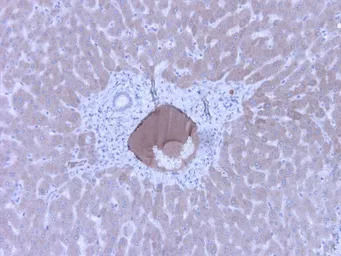

IHC staining of human kidney with GTX49368. Strong staining of veins of nephritis kidney. Dilution: 1:600.